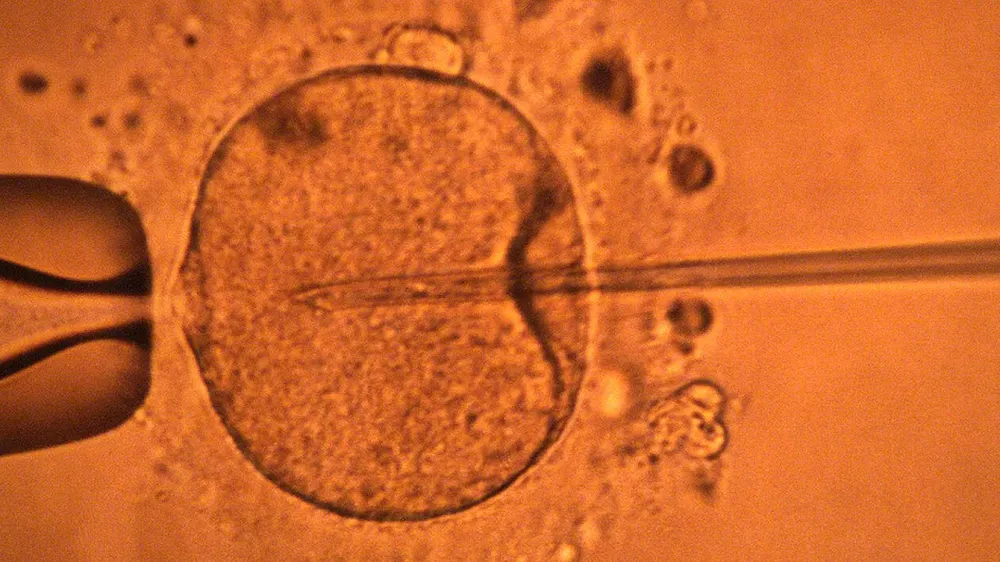

Genetik olarak özdeş bireyler yaratmak amacıyla somatik hücre klonlama teknolojisi kullanılarak Ekim ayında üretilen döllenmiş yumurtalar, taşıyıcı anne domuzun rahmine nakledildi. Üç domuz yavrusu sezaryenle doğdu.